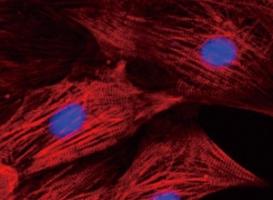

Actualité publiée il y a 10 années 3 moisCELLULES SOUCHES: Utiliser la peau pour sauver le cœur